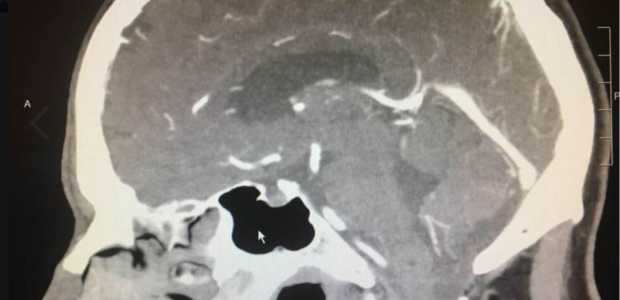

Faith Community Stunned After Man’s Brain Tumor Miraculously Disappears

Doctors were left stunned after a recent exam revealed a California man’s brain tumor had completely disappeared. A few months … Continue reading Faith Community Stunned After Man’s Brain Tumor Miraculously Disappears